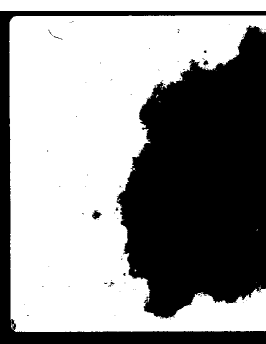

Fig. 3 shows the output of four particular ensembles: Otsu-Kapur-Huang, Yen-Sahoo-Li, Otsu-Kapur-Huang-Yen, and Huang-Yen-Sahoo-Li. Note that each ensemble contains at least one method that either underestimates or overestimates the optimal threshold. It can be seen that each ensemble performs equally well, which demonstrates that failures in pathological cases might be prevented using a proper fusion strategy.

Refer to caption

(a) Otsu-Kapur-Huang

(b) Yen-Sahoo-Li

(c) Otsu-Kapur-Huang-Yen

(d) Huang-Yen-Sahoo-Li

Figure 3: Comparison of various threshold ensembles